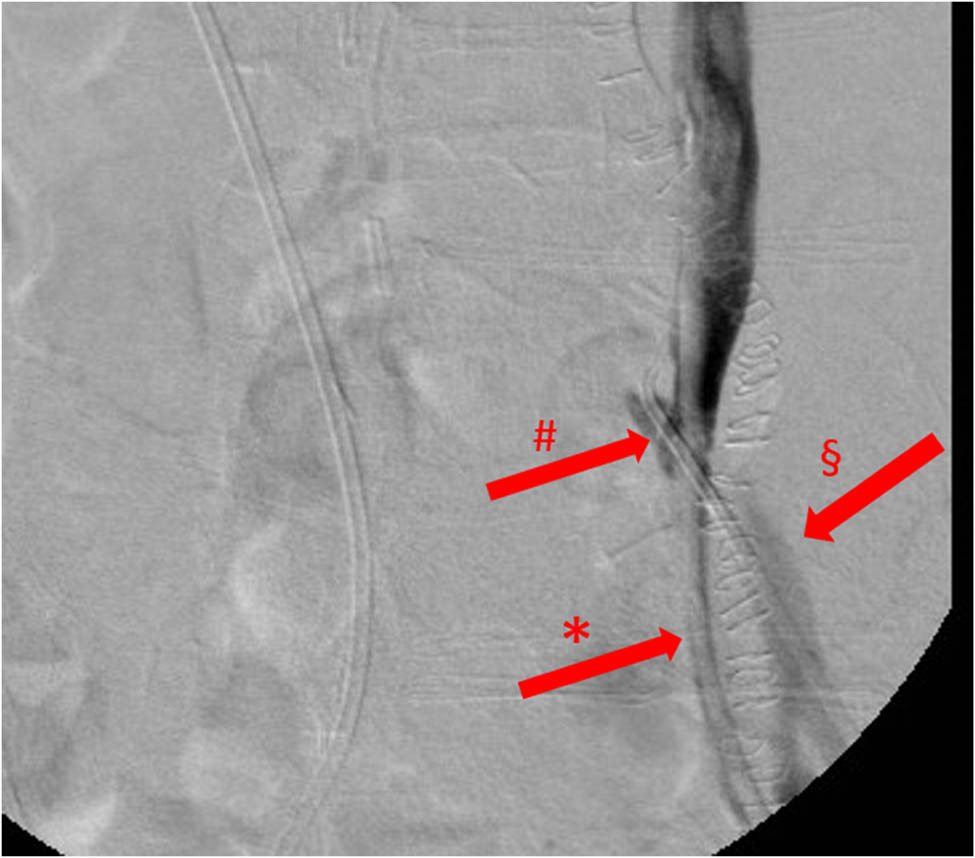

Figure 4

Retrograde ureterography, image with no digital subtraction, frontal view, case 2, first episode. Iodinated contrast leak from the left ureter into the distal left common iliac artery. *: left ureteral stent; §: left common iliac artery; and #: UAF.

A 56-year-old Caucasian woman underwent hystero-adnexectomy plus pelvic lymphadenectomy and adjuvant radio-chemotherapy treatment for squamous cell carcinoma of the uterine cervix in 2000. The patient, suffering from post-actinic retroperitoneal fibrosis and hydronephrosis was treated by bilateral ureteral stenting in 2007. In 2014, the patient underwent left radical nephrectomy (RN) for chronic pyelonephritis associated with severe haemorrhage. Few months after RN, the patient was re-admitted to our clinic for gross haematuria reaching a haemoglobin level of 6.6 g/dL, thus requiring blood transfusions. CT angiography and retrograde pyelography resulted negative for contrast leakage, so a bilateral ureteropyeloscopy and provocative retrograde pyelography were performed: the latter manoeuvre showed contrast leakage from the left ureteral stump into the iliac artery (Figure 4).

In our second case, ureteroscopy with retrograde pyelography was diagnostic for UAF, while CT was negative. When the UAF has risen again, the arteriography initially was negative, whereas resulted positive during combined endourological-endovascular surgery. CT scan in the second episode was not practiced since, in the concrete suspicion of a UAF and because of the patient’s severe renal failure, priority was given to the angiographic study, thus allowing performing simultaneously both diagnosis and treatment (Table 4).